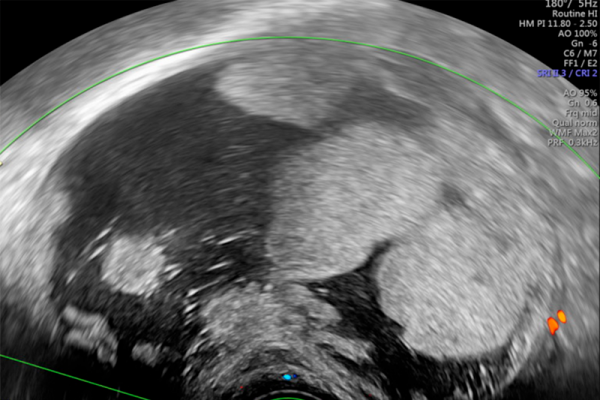

Ecografía en el diagnóstico de la patología ovárica y masas anexiales

La ecografía ha cambiado en poco tiempo la práctica del seguimiento prenatal aún cuando ha costado más su generalización en el ámbito del diagnóstico ginecológico. De hecho, ha estado limitada durante mucho tiempo a confirmar los embarazos intrauterinos y a ayudar en el diagnóstico de masas anexiales. Sin embargo, los rápidos progresos técnicos, que van acompañados de una gran profusión de publicaciones científicas han permitido ampliar actualmente su campo de actuación. Este hecho obliga a los profesionales que trabajan en el área del diagnóstico ecográfico de la patología ovárica y diagnóstico diferencial de las masas anexiales a mantener un proceso de formación y reciclaje continuado, ya que se trata de patologías muy frecuentes cuyo diagnóstico incorrecto puede ser causa de intervenciones quirúrgicas innecesarias.

Conocer la calibración y uso correcto de la ecografía ginecológica en la valoración del ovario y los anejos. Actualizar el conocimiento en el diagnóstico de la patología ovárica y el diagnóstico diferencial de las masas anexiales, en particular, así como en los trastornos derivados del funcionalismo.

Unidad 2- Terminología y sistemas de clasificación de las masas: IOTA. GI-RADS, O-RADS. Betlem Graupera

Unidad 6- Patología orgánica benigna del ovario. Meritxell Vila

Unidad 7- Estudio de las masas anexiales sospechosas. M. Angela Pascual